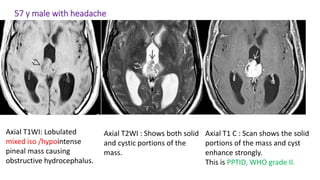

57 y male with headache

Axial T1WI: Lobulated

mixed iso /hypointense

pineal mass causing

obstructive hydrocephalus.

Axial T2WI : Shows both solid

and cystic portions of the

mass.

Axial T1 C : Scan shows the solid

portions of the mass and cyst

enhance strongly.

This is PPTID, WHO grade II.